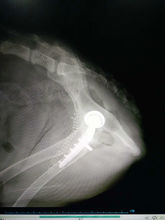

2、后期治疗包括使用股骨头颈切除手术(femoral headand neck ostectomy ,FHO)和犬全髋关节置换手术(total hip replacement THR)。

使用股骨头切除手术是一种通过股骨头切除使得髋关节不会磨损和疼痛的手术,是在1965年开始使用的一种技术,至今仍被使用